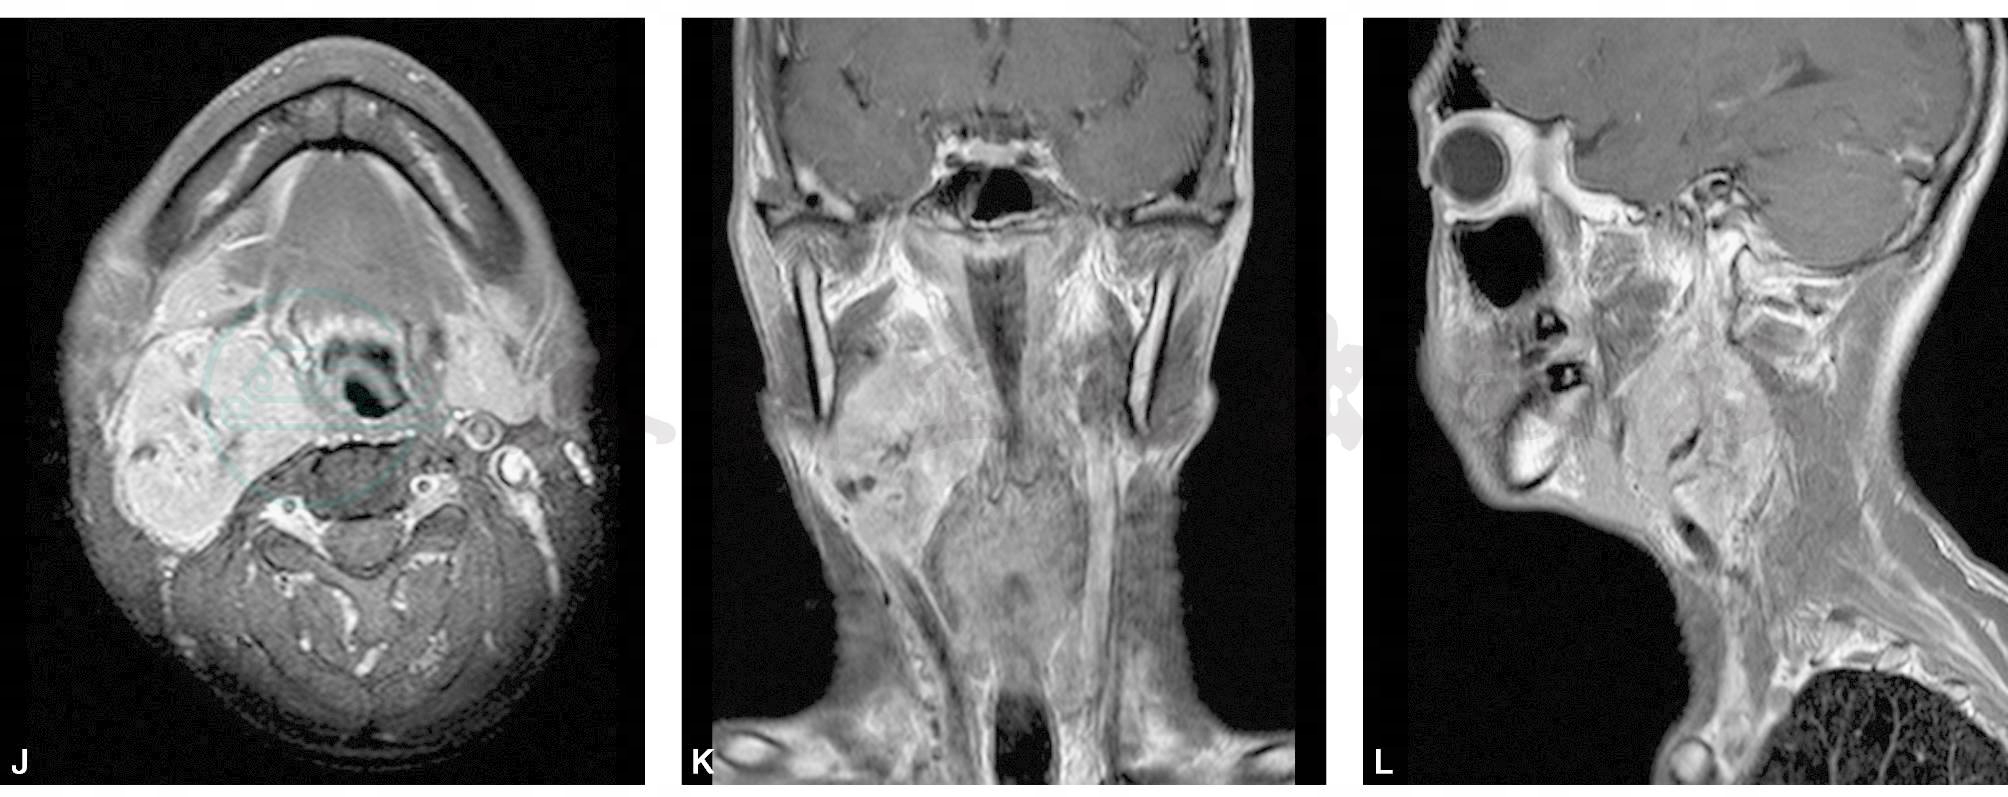

MRI:右侧口咽旁见一肿块影,边界清,呈浅分叶状,T1WI、T2WI均呈等信号为主混合信号,其内可见长T1短T2点状及条状流空血管影,呈“胡椒盐”征(图1H~J)。动态增强病变实性部分呈渐进性强化(图1K~L)。右侧口咽旁间隙受压向内侧推移,右侧颈总动脉及颈外动脉近段被肿块包绕,右侧颈内静脉明显受压变扁并向右侧移位。

图1 咽旁颈动脉体瘤

A.横轴位平扫;B.横轴位动脉期增强;C.横轴位静脉期增强;D.冠状位增强;E.矢状位增强;F. CTA重建图;G. T1WI横轴位平扫;H. T2WI横轴位平扫;I. T2WI脂肪抑制冠状位;J. T1WI横轴位增强;K. T1WI冠状位增强;L. T1WI矢状位增强